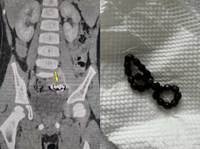

¡°¹è ³Ê¹« ¾ÆÆÄ¡± 4»ì ³²¾Æ¡¦ ¹î¼Ó¿¡ ¡®À̰͡¯ ÇѰ¡µæ ÀÖ..

º¹ÅëÀ» È£¼ÒÇÏ´ø ³²¾ÆÀÇ ¹î¼Ó¿¡¼ ÀÚ¼® ¹¶Ä¡°¡ ¹ß°ßµÈ »ç·Ê°¡ º¸°íµÆ´Ù. ¿À¸¸ ¼ÒÇϸ£ º´¿ø ¼Ò¾Æ°ú ÀÇ·áÁø¿¡ µû¸£¸é, 4¼¼ ³²¾Æ°¡ 1³â°£ Áö¼ÓÀûÀÎ º¹ÅëÀ» °Þ¾ú´Ù. Ãʱ⿡´Â ´Ü¼ø º¯ºñ·Î ÆÇ´ÜµÅ °ü·Ã Ä¡·á¸¦ ¹Þ¾ÒÁö¸¸, ..